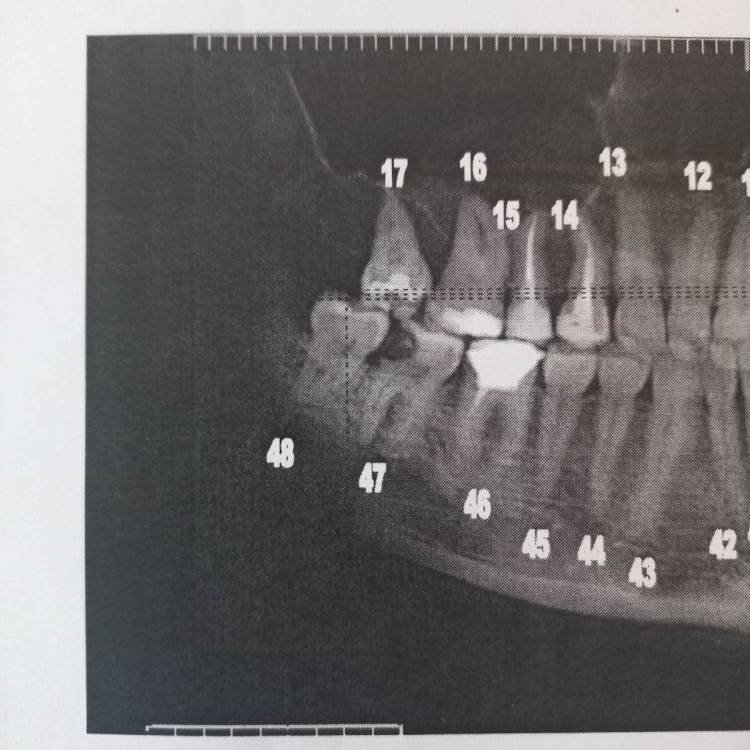

Еленаkjj Опубликовано 18 декабря, 2022 Поделиться Опубликовано 18 декабря, 2022 Здравствуйте! Нужно удалить 38-ой зуб и возможно 48 (один доктор сказал, что можно вылечить). Решение вопроса осложняется непереносимостью анестезии с адреналином и общим состоянием здоровья (заболевание печени, синдром активации тучных клеток). Общий наркоз и седация (большая лекарственная нагрузка) тоже противопоказана в связи с общим состоянием здоровья. Анестезия без адреналина (ультракаин Д, скандонест) действует, но слабо и недолго. Недавно удаляла корни разрушенного 26-го зуба под ультракаином Д. Длилось это минут 40. Корни распиливали и удаляли по одному. Было больно. На последнем корне было настолько больно, что колотящееся сердце остановилось, потемнело в глазах, до обморока не дошло, но было близко к тому. Я резко села на кресле, стала часто дышать и немного отпустило. Потом еще час было общее плохое состояние. 38-ой зуб сильно разрушен внутри. Там разрушение идет почти по всему периметру зуба, между коронкой и десной образовалась кариозная полоса. Зуб живой. С учетом непереносимости адреналина и недавнего болезненного опыта удаления 26-го с анестезией без адреналина стоит ли попробовать удалить 38-ой зуб с помощью ультразвука? Поможет ли такой метод минимизировать в моем случае боль и какие противопоказания у ультразвука? Ссылка на комментарий